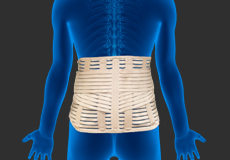

Lumbar Spinal Bracing

Lumbar braces are external devices used to restrict the movement of the lumbar spine and provide support and stability to the lower back region, to relieve back pain and promote healing after surgery or injury.

Cervical Bracing

Cervical braces are external devices used to provide support and restrict movement of the cervical spine in a variety of cervical conditions ranging from muscle spasm to severe spine instability or post-surgery. Braces are also called orthotics and are made from different materials such as nylon, rubber, moulded plastic and elastic cotton.